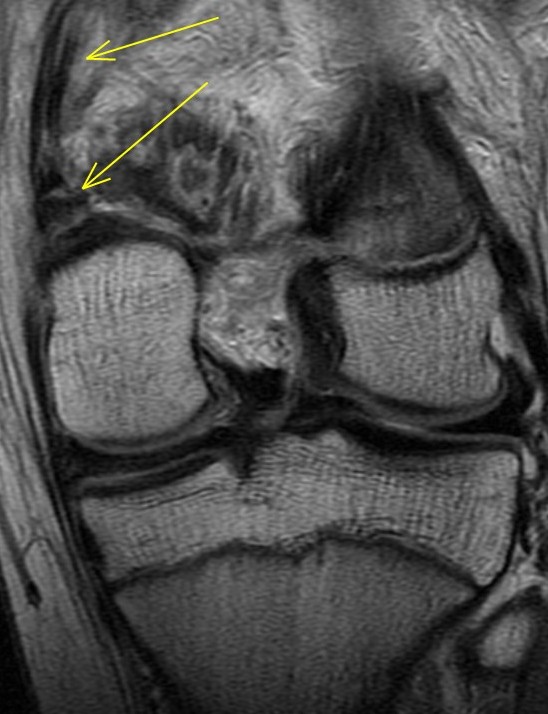

14 y/o tackled from the side after blocking a field goal in American football

The adductor magnus insertion is avulsed and there is fluid within the physis consistent with a SH injury (probable type 2 although its a bit tough to say whether the fragment was metaphyseal or epiphyseal). There was also subperiosteal blood laterally. Orthopedist saw an ossicle on plain films. Alignment good and no ACL or meniscus so he will be put in a brace and treated conservatively. Father asked if he could play in 3 weeks. I said nope.

Avulsion fracture of the adductor magnus insertion